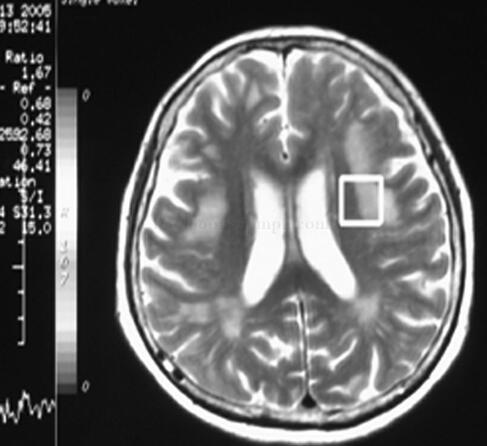

图2球囊扩张并植入支架1枚

图3球囊扩张并植入支架1枚

图4球囊扩张并植入支架1枚

治疗:手术中给予抗过敏,抗休克治疗,与家属积极沟通后,心电监护下顺利行球囊扩张并植入支架1枚,术后病人安返病房,监测生命体征平稳,2天后恢复良好出院。